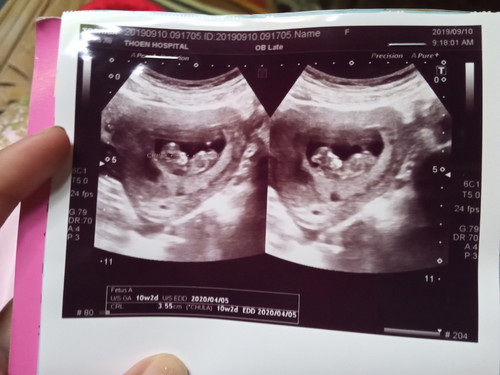

EFW คือการคาดคะเนน้ำหนักทารกในครรภ์ค่ะ จากภาพซาวด์คุณแม่ไม่เห็นตัวย่อนี้นะคะ ตัวย่ออื่นๆดูได้จากในลิงค์นี้ค่ะ https://www.amarinbabyandkids.com/pregnancy/acronym-ultrasound/2/